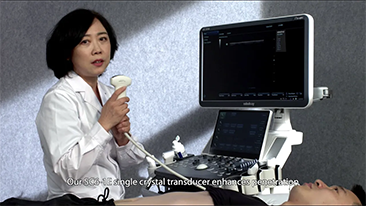

Le soluzioni Mindray Resona per la diagnostica per immagini generale consentono ai medici di ottenere diagnosi e trattamenti con risultati pi├╣ precisi ed efficaci grazie a sonde specifiche complete e a efficienti strumenti clinici applicativi.